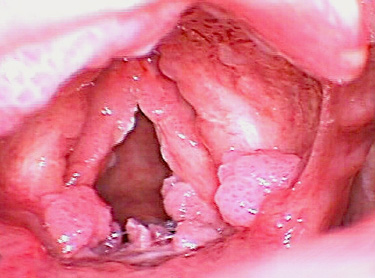

울퉁불퉁하여 사마귀처럼 보이는 양성종양인 유두종은

초기에 쉰 목소리가 나타나며 단발성은 정상 상피가 단순히 이식증식을 일으킨 것이고 다발성 유두종은 소아에게 주로 발생하며 재발이 심하고

넓게 분포가 되어 있으면 호흡곤란증세가 올 수 있습니다.